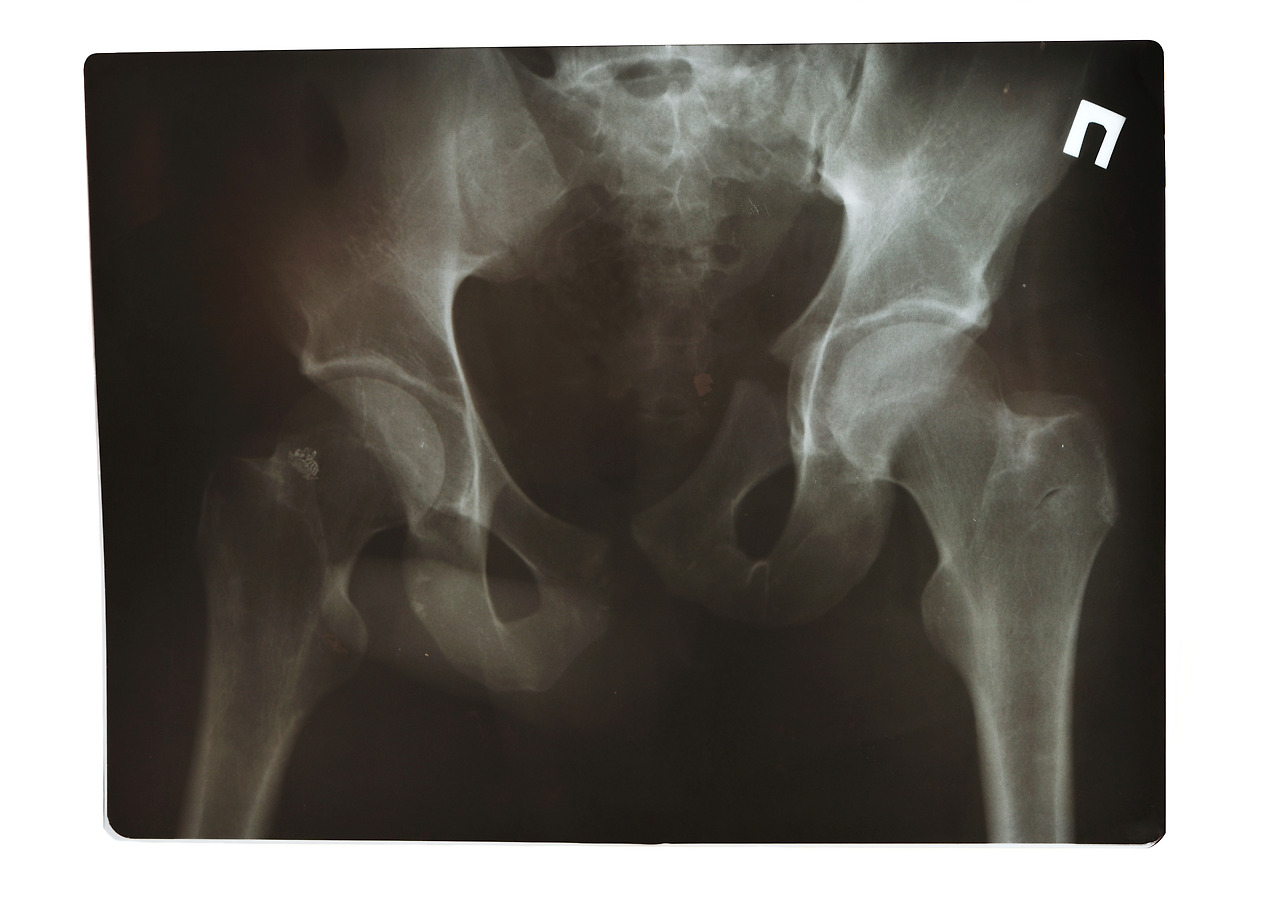

평소와 같이 자동차정비 업무 중 장시간 쪼그려 앉아 있다가 일어나는 순간 고관절 통증이 심해져 거동에 불편함을 겪는 상태로 본원에 내원하신 환자 분이셨습니다. 허리 질환과 고관절 질환의 정확한 감별진단을 위해 고관절 굴곡과 외전, 외회전 신체검사를 진행했습니다. X-ray와 MRI 촬영 결과 허리디스크와 고관절 충돌증후군 진단을 내렸습니다. 특히 오랜 시간 쪼그려 앉는 동작이 반복되면서 나타난 결과로 볼 수 있었습니다.

고관절 충돌증후군은 오래 앉아 있거나 서 있는 시간이 많은 분에게 발생하기 쉽습니다. 초기에는 증상이 심하지 않아 방치되기 쉽지만 만성화될 수 있어 주의가 필요합니다. 크게 대퇴골 두가 변형되어 관절 손상이 나타나는 캠(Cam) 상태와 비구가 변형되어 관절 손상이 나타나는 핀서(Pincer) 상태가 있습니다. 초기 상태라면 비수술적치료가 가능하며 통증의학과 전문의의 진단 및 처방이 선행되어야 합니다.